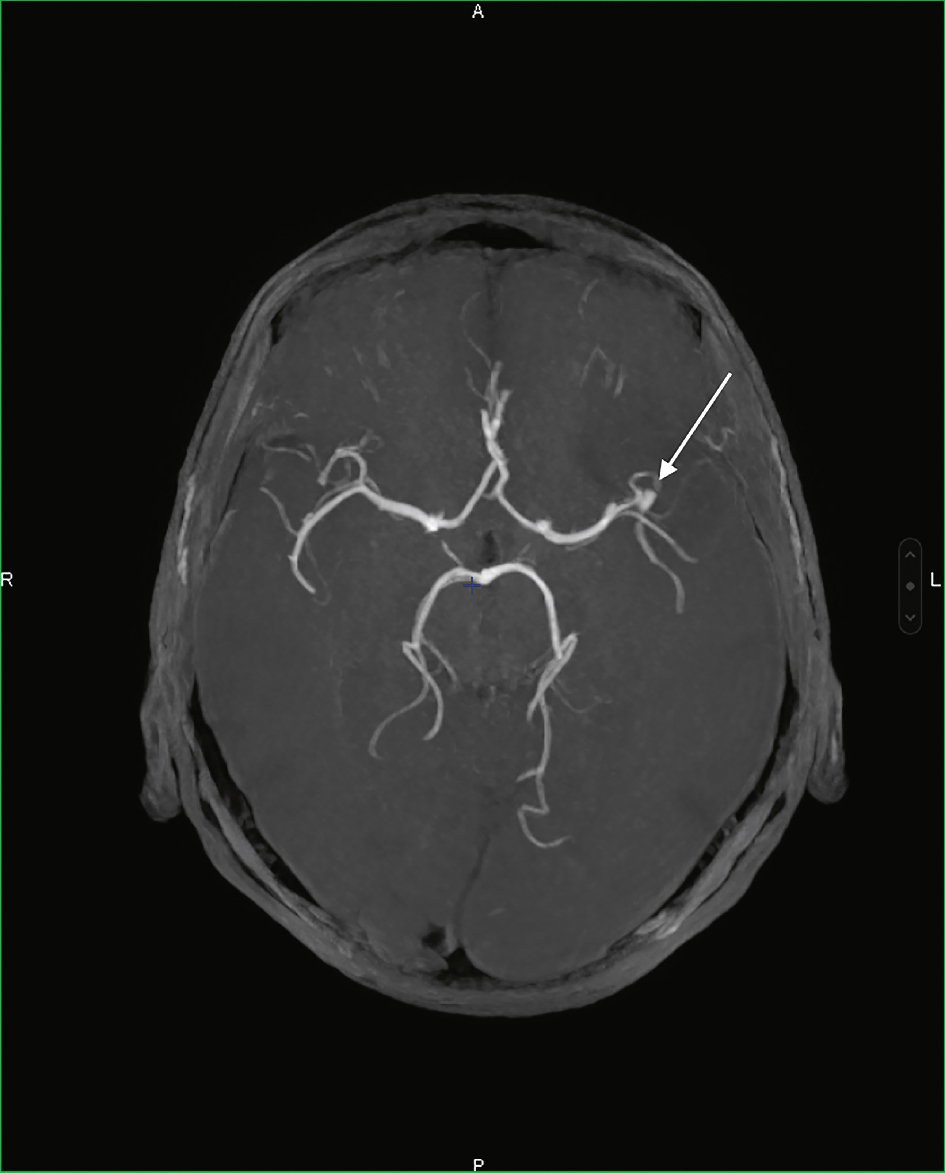

L’angioscanner ou l’ARM permettent de visualiser dans la majorité des cas la présence de l’anévrisme artériel (image d’addition, fig. 29.3).

Fig. 29.3

Angiographie par résonance magnétique cérébrale montrant un anévrisme de l’artère cérébrale moyenne gauche (flèche).Image d’angiographie par résonance magnétique cérébrale en vue axiale, centrée sur le polygone de Willis. Les principales artères intracrâniennes sont bien visibles en hypersignal, permettant une analyse fine de leur morphologie. Une flèche blanche pointe une dilatation focale localisée sur le segment bifurcationnel de l’artère cérébrale moyenne gauche, compatible avec un anévrisme. Cette image met en évidence la capacité de l’ARM à détecter les anomalies vasculaires intracrâniennes sans injection de produit de contraste iodé, en visualisant nettement les structures artérielles cérébrales dans leur continuité et leur calibre.

- • L’angiographie conventionnelle, ou artériographie cérébrale par cathéterisme artériel, est réalisée lors du traitement de l’anévrisme ou à visée diagnostique dans certains cas où l’étiologie reste incertaine.